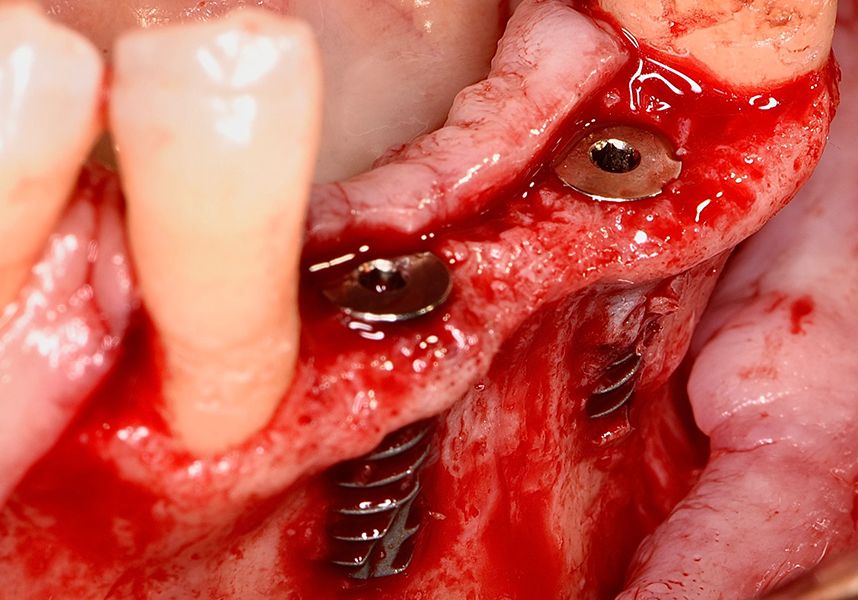

To treat the defect, bone regeneration was carried out simultaneous to the surgical process, with an autologous bone graft from the patient. In the internal part of the graft we used autologous cortical bone obtained by scraping (Safescraper) and from the biological drilling, at low revolutions and without irrigation, from the other implant beds. In the external layer of the regeneration we used a xenograft (Genoss, Osteogenos) and this was covered with a reabsorbable collagen barrier membrane (Evolution STD, Osteogenos).

The membrane was sutured with PGA reabsorbable suture to the periosteum to secure it, thus avoiding subsequent reentry to remove fixings such as tacks.

In the posterior sector three Biomimetic Ocean IC implants of 4.0x10 were inserted in positions 36, 34 and 46 with delayed load. A small regeneration was also carried out with autologous bone in the implant in position 34, where there was no exposure, but the vestibular cortical was very fine after implant insertion.